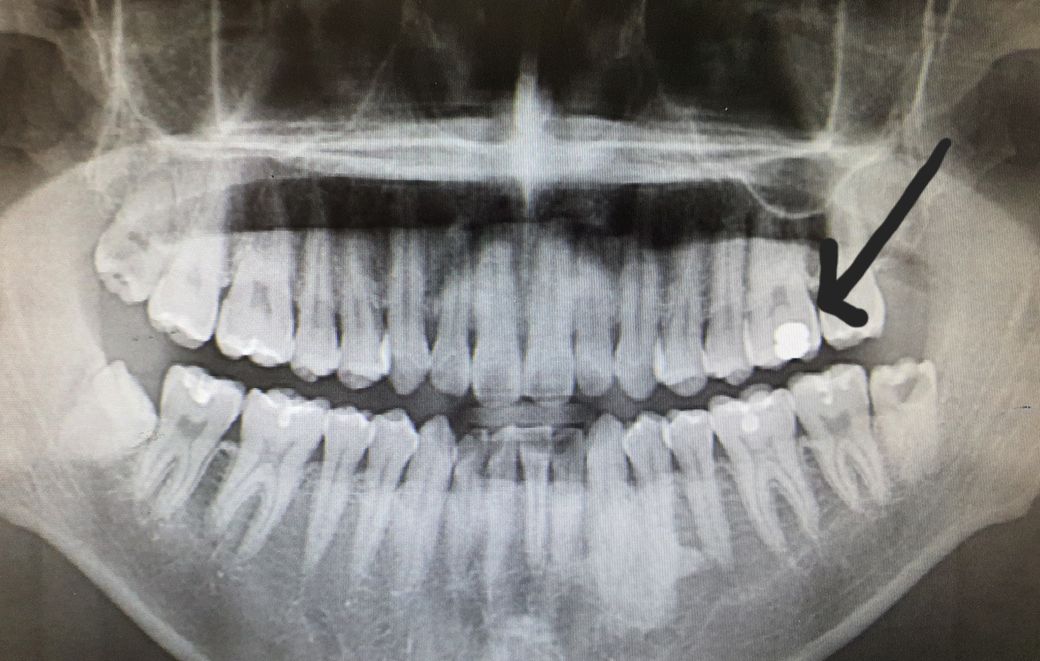

엑스레이 상 왼쪽 윗어금니 아말감 치료 후속

엑스레이 상 왼쪽

어금니에 아말감 치료를 했었는데요,

충치가 진행된 것처럼 보이시나요? 신경치료까지 해야하는 것일지 궁금합니다.

엑스레이 상으로는 크게 충치가 진행된것처럼 보이진 않지만, 아말감 상태가 좋지 않다면 제거후에 다시 치료를 하시는게 좋을것같습니다.

1. 이차충치와 관련해서는 환자분의 증상(차갑거나 뜨거운 음식 먹을 때 불편한지, 씹을 때 불편한 지)과 치근단방사선사진(위의 사진은 파노라마 방사선 사진이고 좀 더 작은 해상도가 좋은 사진)이 진단에 도움이 됩니다.

2. 현재로서는 아말감 치료 당시 충치가 다소 깊었고 하방에 신경과 보호막을 형성하기 위해 이장재를 깔아둔 것 같습니다.

사진으로만 봤을 경우에는 아마감 주변에 충치가 보이지는 않습니다.

충치가 진행된 것으로 보이고 신경치료 가능성도 높아보입니다. 정확한 것은 아말감을 제거해봐야 압니다.